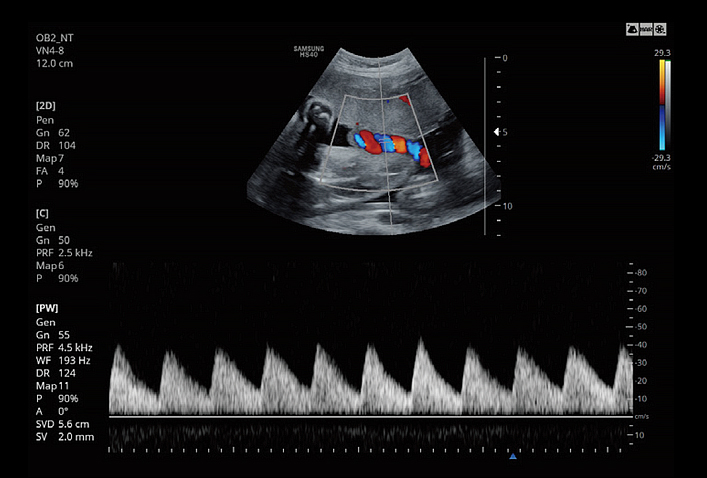

5D NT™ provides the midsagittal plane view automatically by rotating and magnifying the images when measuring the nuchal translucency (NT) of the fetus in early weeks.

LaborAssist™ is a function that provides information of the progress of delivery by the automatic measurement of AoP (Angle of Progress) and the direction of the fetal head. This not only helps in effective communication between the healthcare professionals and mothers, but also assists in deciding a delivery method for the healthcare professionals.